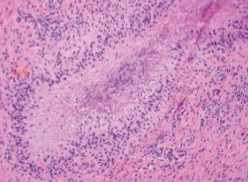

Histology: palisaded granuloma with central fibrinoid necrosis

Rheumatoid nodules